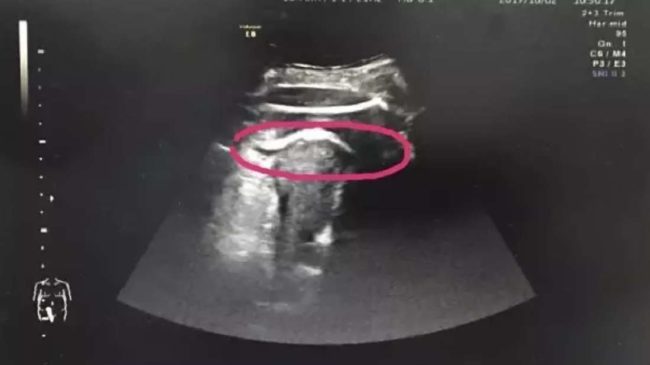

After disclosing her previous medical history with her doctors, it was suggested that the woman undergo an ultrasound to ensure she wasn’t suffering from a ruptured uterus.

In a matter of minutes, Zhang was rushed to an operating table, where doctors discovered that the unborn fetus’ legs were poking into her abdominal cavity.

According to doctors, the woman’s previous surgeries had left her with severe scar tissue that left the uterus wall more at risk of breaking.

Such a break is known as a rupture pregnancy and impacts less than 5 out of every 1,000 pregnancy women who have had previous Cesarian work.